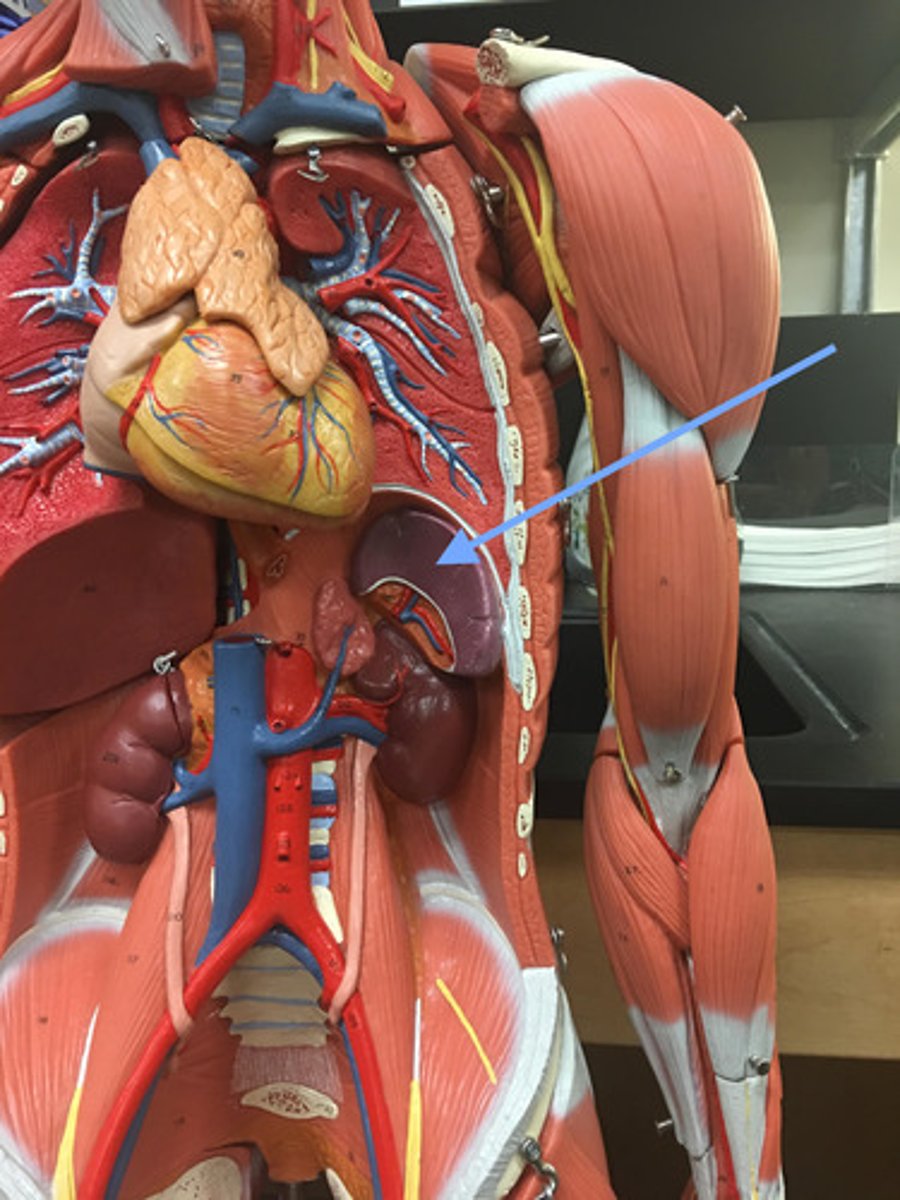

spleen

-the major function of this organ is to scrutinize the incoming blood for aged and malformed erythrocytes

-Will remove RBC and recycle their iron and begin disposal of bilirubin.

-On the lookout for any pathogens organisms or toxic materials in the blood.

splenic artery

-extends from the celiac trunk to the splenic hilum.

-supplies to the spleen

splenic hilum

site located in the middle of the spleen where blood vessels, lymphatic vessels, and nerves enter or exit the organ.

splenic vein

-Fuses with the superior mesenteric to carry newly filtered blood to the hepatic portal which will bring it to the liver

red pulp (spleen)

-is the dark red tissue in the spleen containing sinusoidal capillaries, connective tissue fibers, and immune cells like macrophages, plasma cells, and lymphocytes.

-It destroys old red blood cells, removes pathogens and toxins

-facilitates lymphocyte movement between splenic tissue and blood.

white pulp (spleen)

has whitish appearance in a fresh spleen. Lymphocytes, macrophages surrounding small branches of splenic artery